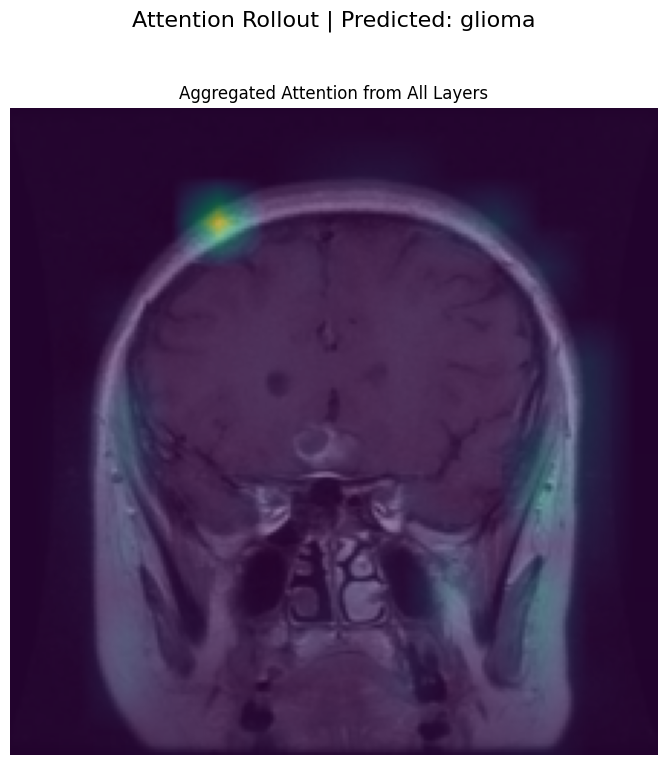

5. Attention Rollout

A Vision Transformer (ViT) is composed of multiple layers of self-attention. While it’s tempting to just look at the final layer’s attention map to see what the model is focusing on, this can be misleading. The final layer’s attention is applied to embeddings that are already a complex mixture of the initial embeddings from all previous layers.

Attention Rollout is a technique proposed by Abnar & Zuidema (2020) to better approximate the full attention flow through the network. It aggregates the attention matrices from all layers to create a single map that shows how much each input token contributes to the output tokens.

(torch.matmul)the current layer’s attention with the accumulated rollout. This composes the attentions across layers, so we capture how attention paths stack together as we move deeper in the network. - We extract how the CLS token looks at the image patches After processing all layers, rollout contains the cumulative influence of each token on every other token.

rollout[:, 0, 1:]selects:- Row 0 → corresponds to the CLS token.

- Columns 1: → corresponds to the patch tokens (ignoring CLS itself). This gives us the final attention rollout map showing which image patches the CLS token (used for classification) is attending to, across the whole network.

Generating Visualization: Attention Rollout: